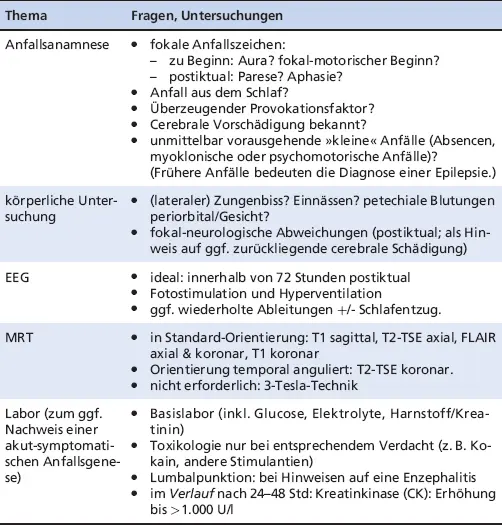

Nach einem ersten Anfall sind nach Bast et al. (2017) die in Abbildung 1.2 dargestellten Fragen zu beantworten. Die in Tabelle 1.1 genannten Untersuchungen beantworten diese.

Tab. 1.1: Checkliste Basisdiagnostik erster Anfall

ThemaFragen, Untersuchungen

Oft kann bereits nach der Anfallsbeschreibung und körperlichen Untersuchung ein epileptischer Anfall diagnostiziert werden. Eine Hirnbildgebung (akut cCT, im Intervall MRT) und (ggf. mehrere) EEG sind ergänzend immer erforderlich. Die kraniale Bildgebung dient einerseits zur Erkennung behandlungsbedürftiger Ursachen eines akut-symptomatischen Anfalls (z. B. Sinusvenenthrombose), wozu in der Regel eine CT ausreicht. Andererseits trägt die Bildgebung zur Abschätzung der Wahrscheinlichkeit eines Rezidivanfalls mit seinen weitreichenden sozialen Konsequenzen bei (Krumholz et al. 2007; Krumholz et al. 2015). Hierfür ist die sensitivere MRT besser geeignet. Sie wird von der DGN-Leitlinie in ≤ 4 mm dicken Schichten in Standardangulierung (soweit nicht anders angegeben) mit den folgenden Sequenzen empfohlen (Bast et al. 2017):

• T1 sagittal und koronar

• T2 axial und koronar (Letztere temporal anguliert)

• FLAIR axial und koronar

Die Ausbeute an epilepsietypischer Aktivität steigt, wenn das EEG innerhalb von 72 Stunden nach einem ersten unprovozierten Anfall abgeleitet wird (Debicki 2017) oder der Patient in Leichtschlaf fällt (Hoppe et al. 2007a). Das vielfach geübte Vorgehen, hierzu einen vorherigen Schlafentzug zu verordnen, birgt das Risiko einer Anfallsprovokation und ist daher nur bei negativem Routine-EEG inklusive Schlafaufzeichnung vertretbar (Bast et al. 2017). Nach mehr als vier Routine-EEGs ohne epilepsietypische Potentiale ist die Chance, mit einer weiteren Routine-Ableitung epilepsietypische Potentiale zu erfassen, nur noch gering (Debicki 2017).